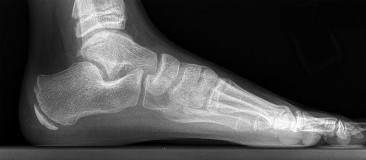

A 14-year-old boy complains of a painful, rigid flatfoot and a history of recurrent ankle sprains. Physical examination demonstrates severe restriction of subtalar motion and peroneal spasticity. A 45-degree internal oblique radiograph of the foot reveals an 'anteater nose' sign. Which of the following is the most likely diagnosis?